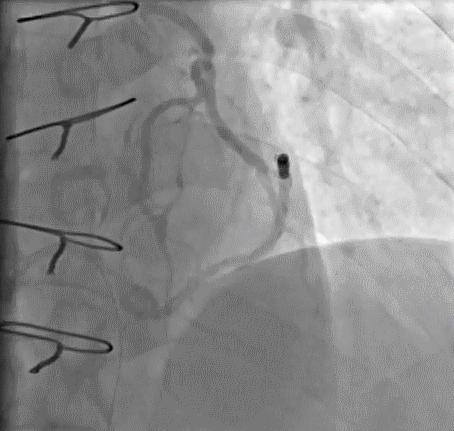

➢ CASE 1

➢ CASE 2

右冠起源异常,开口于左冠窦

➢ CASE 3

AL1.0

➢ CASE 4

➢ CASE 5

升主动脉造影未见桥血管显影,原位血管造影也没发现竞争血流迹象,可以确定桥血管已闭塞,必要时可以借助冠脉CTA辅助诊断